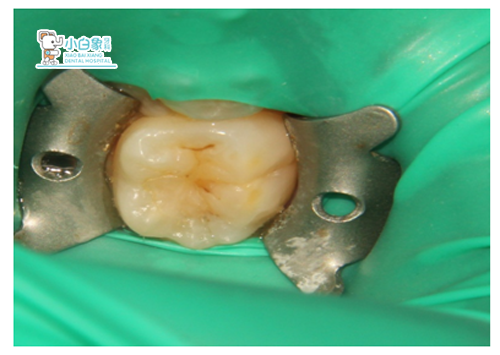

主诉:右下后牙发黑多日,求治。

口内检查:右下后牙合面窝沟龋坏达牙本质浅层,叩(-),温度试验正常,牙龈无红肿。

诊断:中龋

QQ截图20181220150417

治疗过程:表麻膏涂布游离龈及牙龈乳头后,上橡皮樟,去腐质,备洞隔湿干燥,行Z350充填,调合,抛光。